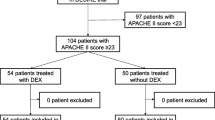

After approval of protocol by institutional Bioethics Committee, observational study was performed in medical and surgical patients in mixed ICU. The inclusion criteria were age 18 years or older, respiratory insufficiency requiring analgosedation and mechanical ventilation and need for the treatment of hyperactive delirium and agitation refractory to haloperidol in intubated and/or extubated ICU patients. Patients were excluded if they were < 18 years old, heart rate was less than 50 beats per minute and they had significant hemodynamic instability. Patients were evaluated according to the APACHE II score and SOFA score and have measured vital parameters: body temperature, heart rate, systolic, diastolic and mean arterial pressure, central venous pressure and urine output. Dexmedetomidine (Dexdor, Orion Pharma Poland Sp. z.o.o.) was infused continuously without a loading dose. The depth of sedation was determined using the modified Ramsay sedation score to maintain the sedation score of 2–3. The infusion of dexmedetomidine was combined with opioids as needed for analgesia. We started the infusion of dexmedetomidine at the rate of 0.8–1 μg/kg/h that was followed by continuous infusion that ranged from 0.4 to 1.5 μg/kg/h. The infusion of sedative was stopped when there was a significant hemodynamic instability, after the patient extubation or at the discretion of the physician. The supply of the drug was modified according to Ramsay sedation score, and each dose adjustment of dexmedetomidine was recorded. Clinical adverse hemodynamic instability was defined as hypotension (a systolic blood pressure less than 90 mmHg and/or mean arterial pressure less than 65 mmHg) and/or bradycardia (heart rate less than 50 beats/min).

This analysis was based on the concentration–time profiles of dexmedetomidine collected from 27 patients (Fig. 1). Table 1 lists the patients’ demographic and the available covariates. The available data consisted of 368 dexmedetomidine concentration measurements (Fig. 1).